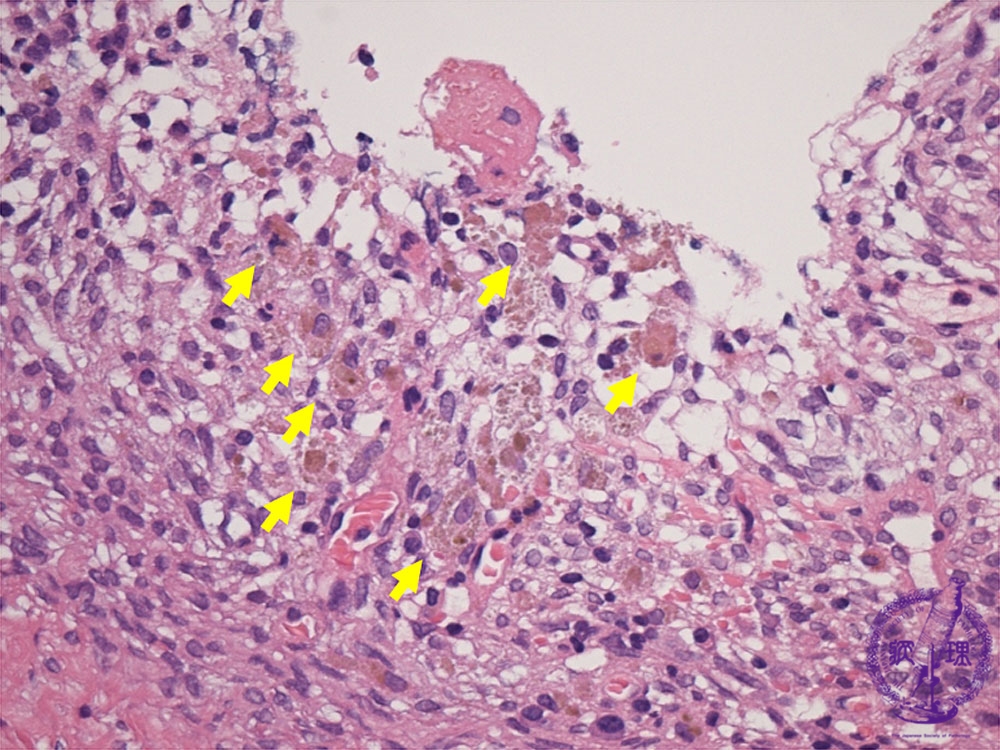

Histology (HE stain, high power): Endometrial stromal tissue and numerous hemosiderin-laden macrophages (yellow arrow) in the cyst wall.